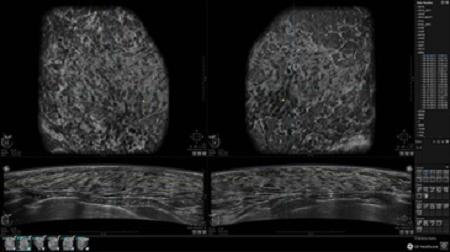

GE INVENIA ABUS – это современный УЗИ аппарат, который создан для точной и эффективной диагностики сканирования с высокой плотностью молочных желез. Выявляемость патологий раковых и предраковых стадий заболевания составляет 55%, что в конечном счете позволяет ставить врачу точные и своевременные диагнозы. Традиционные методы использования маммографии не показывают такой выявляемости, ограничиваясь лишь 3-38%.

УЗИ-аппарат GE INVENIA ABUS позволяет проводить максимально операторонезависимые процедуры, что значительно снижает риск неправильной постановки диагноза и сопутствующие издержки на обработку информации. Система готовит отчет в течение 3-х минут после сканирования, это безусловное преимущество по сравнению с обычным УЗИ сканером.

• Получение изображений в поперечной плоскости (в реальном времени) и в коронарной плоскости (статическая, для указания нахождения соска)

• Многооконный просмотр: 4 - 12 изображений

• Стандартизованная ориентация изображения: «толстый срез» в коронарной плоскости; поперечная; сагиттальная плоскость; радиальный и антирадиальный поворот изображения; просмотр исключительно области интереса

• Одновременный просмотр двух изображений для сопоставления в коронарной плоскости